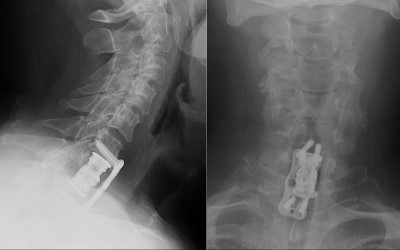

Intraoperative fluoroscopic images (lateral projections) taken during the C7 corpectomy and fusion procedure. Left image shows localizing needle in the C7-T1 disc space. Right images show the expandable interbody biomechanical device (aka cage) being applied. The upper image shows the top of the cage while the lower image shows the bottom.

- Post-op